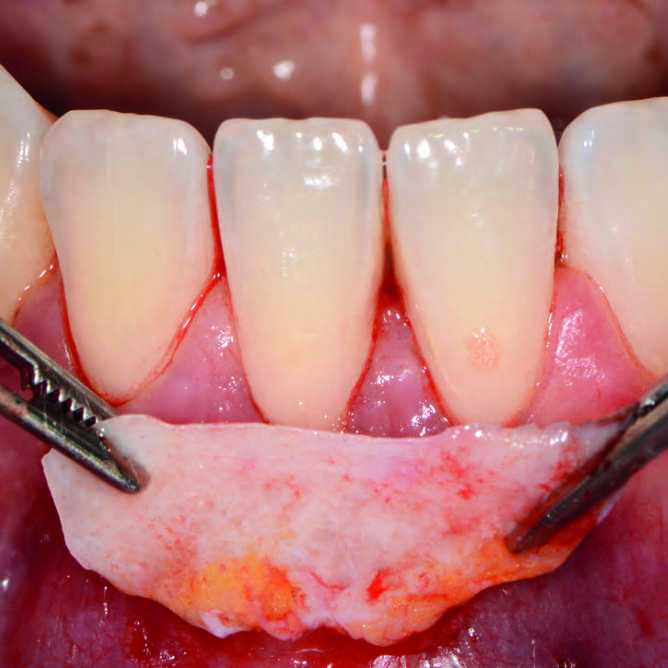

Case Report

Multiple Rezessionsdeckungen mit Kollagenmembran erschienen in Implantologie Journal 10/2021 |